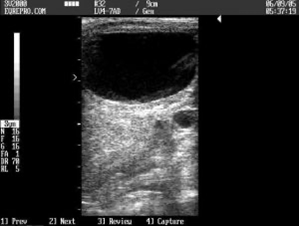

Transrectal ultrasound

- Assessment of ovarian activity

- Detection of cysts or abnormalities

- Evaluation of uterine oedema patterns

- Identification of fluid or signs of inflammation